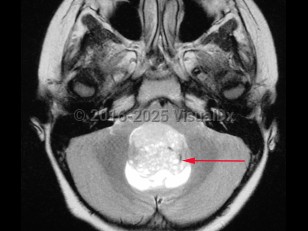

A medulloblastoma is a malignant primary brain tumor located in the posterior fossa near the fourth ventricle. It is the most common malignant brain tumor in children. One-third of cases present in children aged younger than 3 years. In adults, the tumor usually presents before age 40.

Initial symptoms may relate to increased intracranial pressure as a consequence of blockage of the fourth ventricle, causing morning headache, nausea / vomiting, and irritability. Later, patients can develop ataxia, frequent falls, papilledema, diplopia, nystagmus, and/or neck stiffness.

This tumor may spread through the cerebrospinal fluid (CSF) to other parts of the brain and spinal cord. It is an aggressive tumor and recurrence is common. Five-year survival rates are about 60% in all age groups. Patients with medulloblastoma are considered higher risk if they present as infants or at an older age, have metastatic disease, and if their tumors have aggressive histopathology or specific molecular markers.